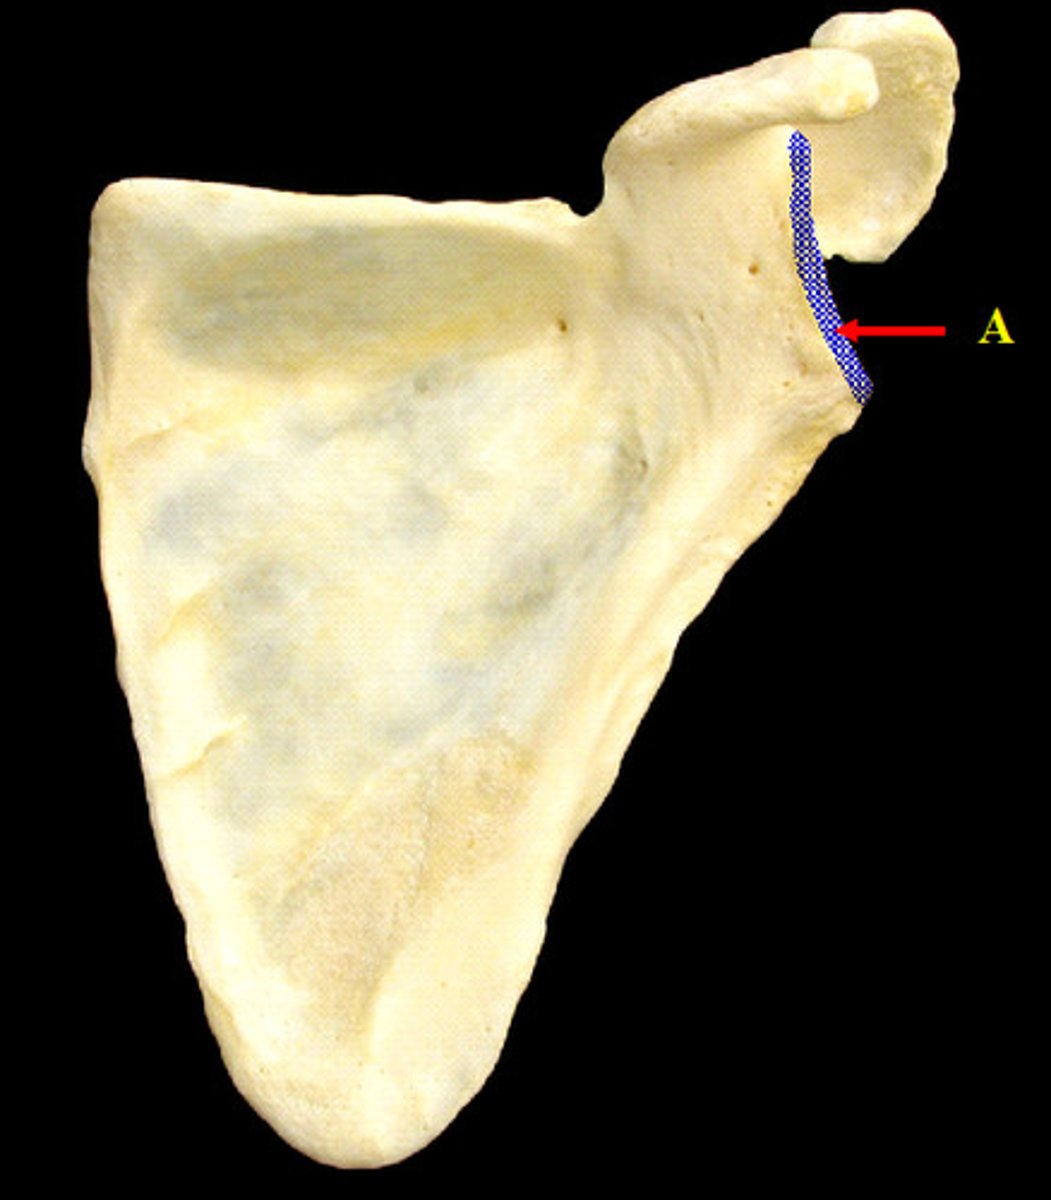

What structures are on the lateral surface of the scapula?

- glenoid cavity

- coracoid process

- head of scapula

- neck of scapula

- suprascapular notch

Suprascapular notch of scapula:

- on lateral surface of scapula

- junction of the superior border with the base of the coracoid process

What is the relationship between the suprascapular notch, superior transverse ligament, and the suprascapular nerve?

the suprascapular notch is converted into a foramen by the superior transverse ligament and serves as a passage for the suprascapular nerve